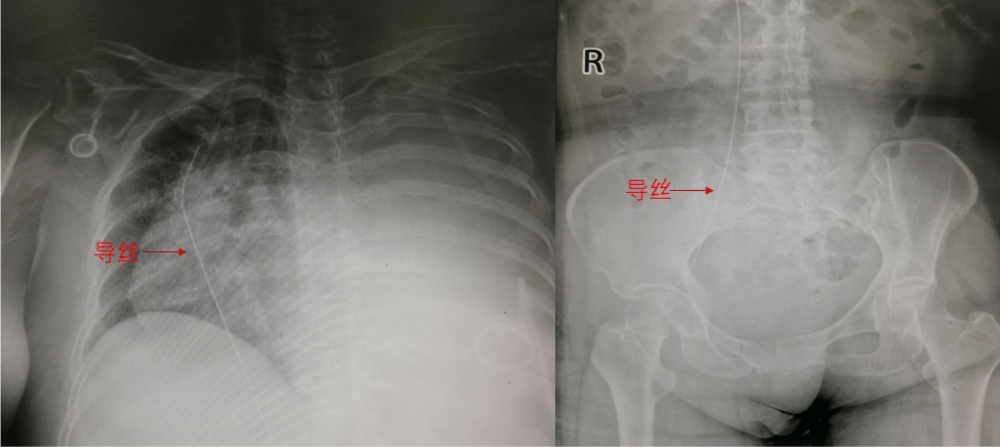

忙碌完一天的手术 , 本来准备下班的冯亚平副主任医师突然接到急诊会诊电话 , 一名小细胞肺癌病人因化疗需要 , 于外院行输液港置入 , 但是在放置的过程中导丝未能妥善固定 , 导致整根导丝进入了静脉内 。 幸运的是 , 胸片可见导丝没有进入心脏 , 而是通过上腔静脉直接进入下腔静脉 , 导丝头端已经到达髂股静脉交界处 。 这种情况下 , 不仅输液港无法继续放置 , 而且导丝留置在体内过久还可能形成血栓 , 进一步导致肺栓塞 , 严重威胁生命 。 所以 , 病人经推荐来我院血管外科 , 寻求帮助取出导丝 。

冯亚平副主任果断决策 , 将病人转运至杂交手术室 。 因为大量胸水 , 患者无法长时间平卧 , 麻醉风险也高 , 所以冯主任选择最微创的方法快速解决问题 。 拟定的手术方案为 , 先进行腔内手术抓捕导丝 , 若腔内方法失败 , 杂交手术室允许迅速转为开放手术 , 切开静脉将导丝拉出体外 。

经局部麻醉后 , 超声引导下穿刺针准确地刺入纤细的大隐静脉 , 建立好通路后准备造影时 , 护士告知因为患者未行碘皮试 , 所以不能进行碘剂造影 。 冯主任考虑 , 如果等待碘皮试 , 患者随时可能发生危险 , 所以他决定仅在透视下进行导丝抓捕 。 冯主任小心地将抓捕器导入股静脉 , 凭借丰富的经验和娴熟的手感 , 成功地将导丝抓住并拉出体外 , 赢得在场医护的喝彩 , 而且整个操作时间仅为2分钟 。 回顾病人救治的整个过程 , 快速转运、手术室的选择、腔内方案的制定和超声的引导 , 最大程度地保证了患者的安全和手术的微创 , 仅给患者留下了一个针眼大小的伤口 。